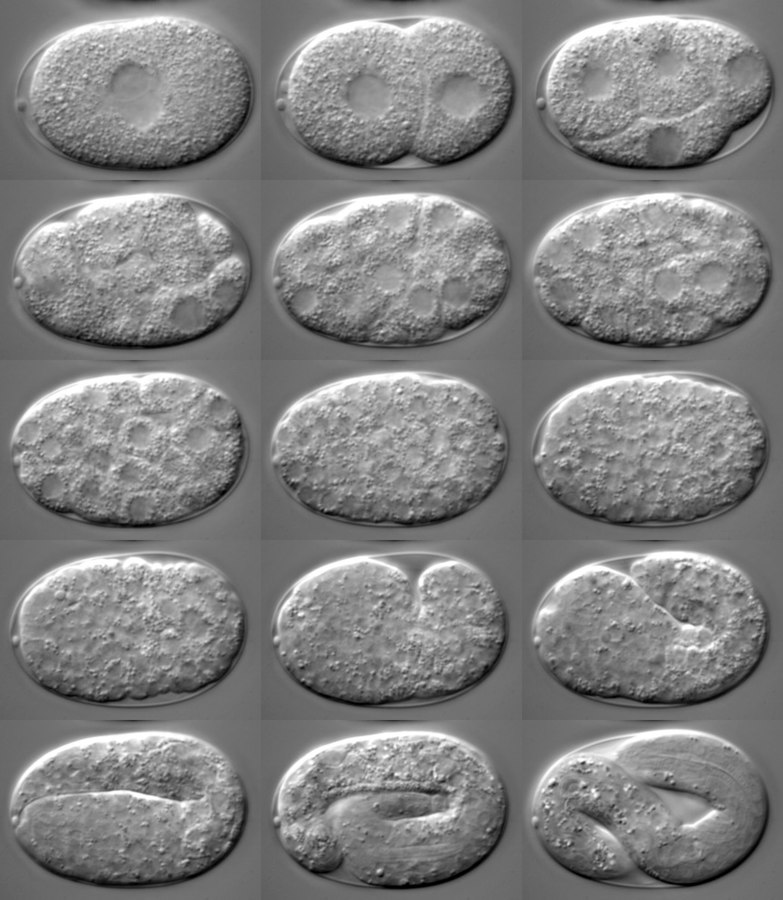

Celý proces tvorby embryí je po technické stránce velice náročný, i proto k podobným experimentům nemohlo dojít již dříve. Díky nové čínské technologii se americkým odborníkům podařilo mimo tělo udržet opičí embrya naživu po několik dnů.

Embrya rostla 6 dnů, následně do nich bylo injekčně vstříknuto 25 lidských buněk. Pod pojmem pluripotentní kmenové buňky se rozumí takové buňky, jež se mohou transformovat v jiný druh buněk, a o to šlo i v tomto případě.

Již jeden den nato byla u 132 embryí zjištěna přítomnost lidských buněk, po dalších 10 dnech se 103 z těchto chimérických embryí stále vyvíjelo. Poté nastal zlom a většina embryí umírala, 19. den experimentu „žily“ už jen 3 chiméry.